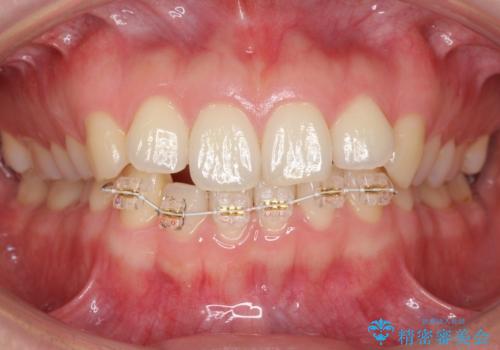

下の前歯が1本短い インビザラインと部分矯正の組み合わせ

- 前歯のガタつきと、下の前歯が一本短いことを主訴に来院。

インビザラインのマウスピースではめる装置で歯を引っ張り出すことは難しいと説明し、下の前歯だけワイヤー部分矯正を行ってからインビザライン矯正で仕上げをしました。